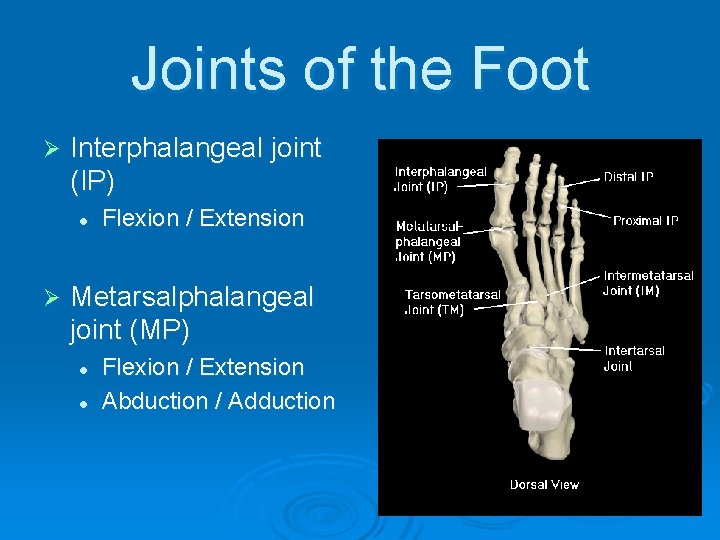

Joints of the Foot Ø Interphalangeal joint (IP) l Ø Flexion / Extension Metarsalphalangeal joint (MP) l l Flexion / Extension Abduction / Adduction